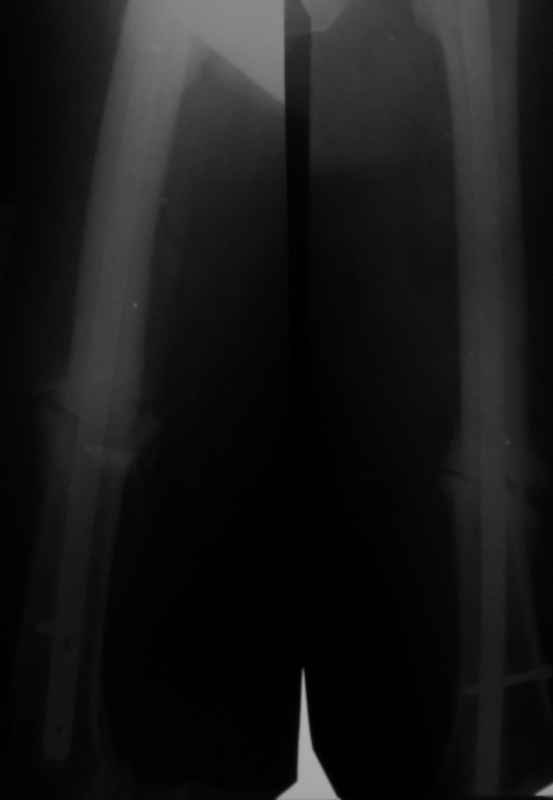

Больной 52л. с переломами обеих бедер 1 годичной давности. Лечился гвоздями Chm.

Справа перелом сросся, слева формируется псевдартроз,ротационная подвижность (после динамизации остался один винт в дистальном отверстии штифта). Активная тактика - удалить гвоздь, рассверлить канал, поставить более толстый. Есть ли ей альтернатива,но не менее эффективная?